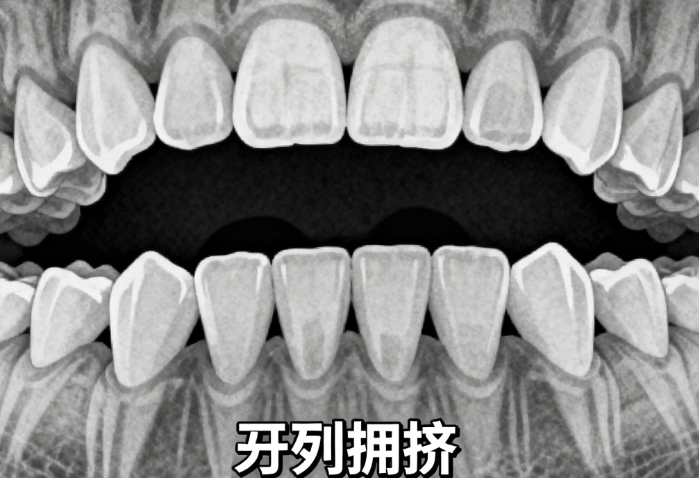

1. 正雅S8基礎(chǔ)款隱形矯正:15000元/全口(含全套矯治器+初診檢查+方案設(shè)計,適合牙齒輕度不齊、牙縫大患者,性價比優(yōu)選);

2. 正雅GS版隱形矯正:18800元/全口(含個性化矯治器+數(shù)字化口掃+定期復(fù)診,適配中度擁擠、輕度深覆合病例);